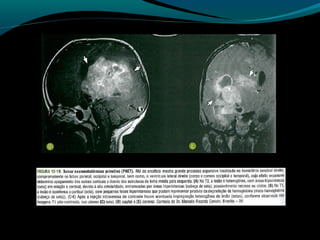

Astrocitoma subependimário de

células gigantes

Raro,

Circunscrito;

Benigno;

De crescimento lento;

Associação com esclerose tuberosa!

TC:

Próximo ao forame de Monro (mas existe localização

atípica);

Expansiva e >1,5cm;

Iso ou hipodensa; pode ser heterogênea e apresentar

calcificações;

Realce intenso pelo contraste;

Suspeitar de tumor quando:

Em pacienetes com esclerose tuberosa, nódulo aumento

de tamanho e tem maior realce em exames seriados;

RM:

Baixo sinal em T1;

Alto sinal em FLAIR e T2 (ou heterogêneo se

hemorragia ou calcificações);

Regra: realce intenso e difuso pelo Gd;

RM:

Geralmente sem disseminação pelo LCR;

Aumento de Co/Cr

Redução de NAA/Cr

Picos de lactato;

Aumento da perfusão;